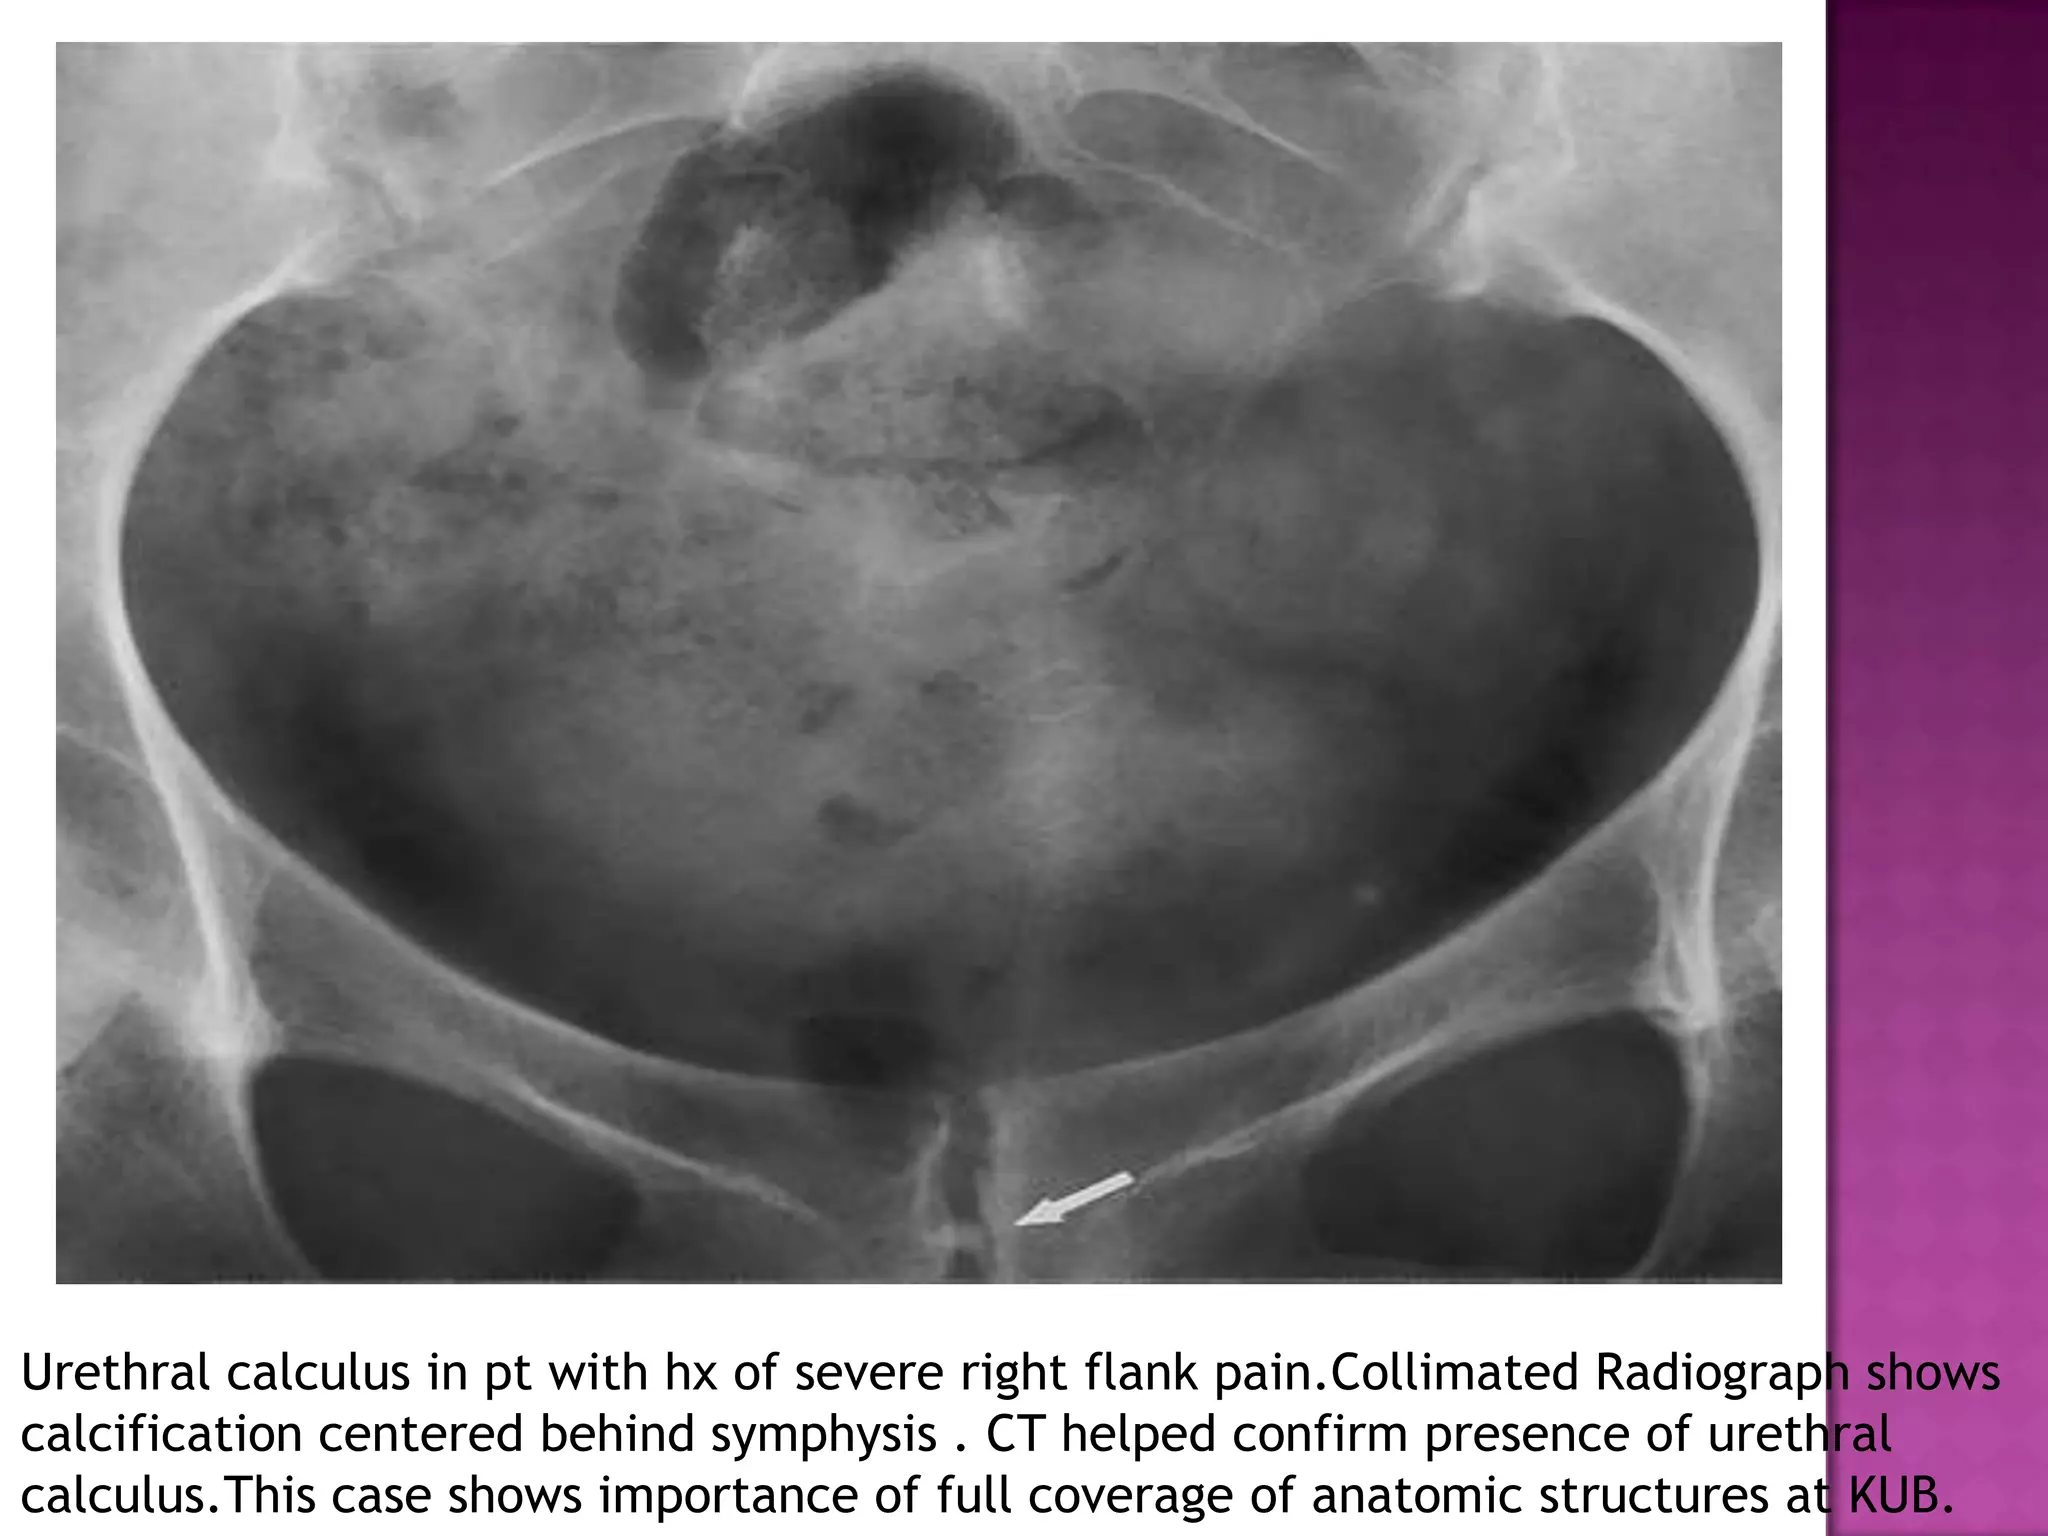

Urethral calculus in pt with hx of severe right flank pain.Collimated Radiograph shows

calcification centered behind symphysis . CT helped confirm presence of urethral

calculus.This case shows importance of full coverage of anatomic structures at KUB.